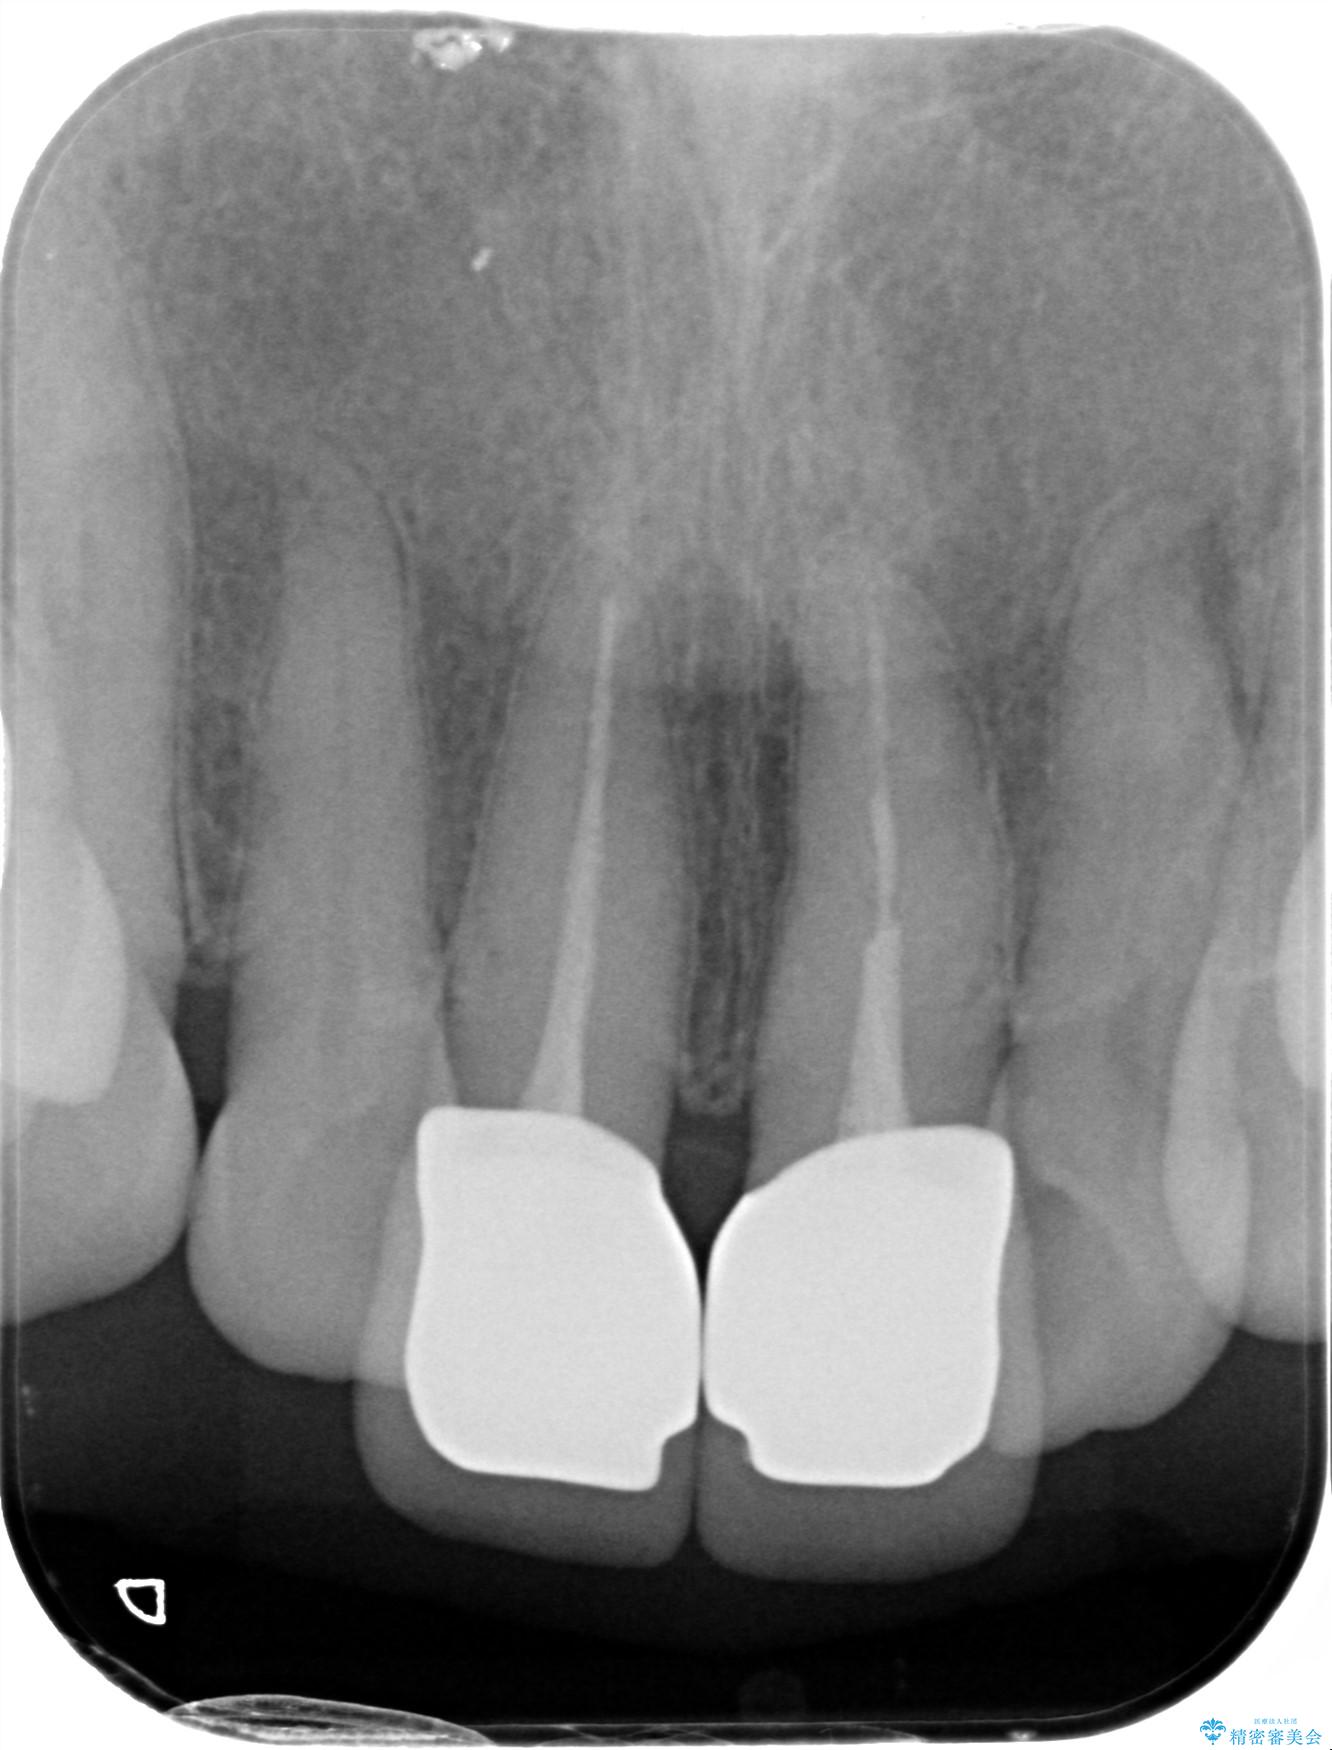

前歯の差し歯(クラウン)が黒ずんでいるとご相談にいらっしゃった患者様です。

根管治療は行わず、クラウンのやり替えのみ行います。